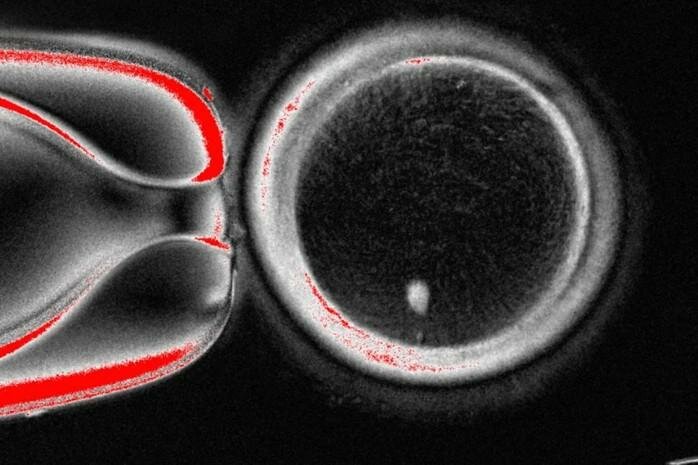

Cụ thể, các nhà khoa học đã lấy nhân (chứa bộ DNA hoàn chỉnh) từ một tế bào da của người, sau đó cấy nó vào "vỏ" của một tế bào trứng đã được loại bỏ nhân. Tuy nhiên, thay vì tạo ra một bản sao y hệt, mục tiêu của họ là "ép" tế bào mới này phải trải qua một quá trình giảm phân, loại bỏ đi một nửa số nhiễm sắc thể để nó có thể sẵn sàng kết hợp với một tinh trùng trong quá trình thụ tinh.

Cụ thể, các nhà khoa học đã lấy nhân (chứa bộ DNA hoàn chỉnh) từ một tế bào da của người, sau đó cấy nó vào "vỏ" của một tế bào trứng đã được loại bỏ nhân. Tuy nhiên, thay vì tạo ra một bản sao y hệt, mục tiêu của họ là "ép" tế bào mới này phải trải qua một quá trình giảm phân, loại bỏ đi một nửa số nhiễm sắc thể để nó có thể sẵn sàng kết hợp với một tinh trùng trong quá trình thụ tinh.